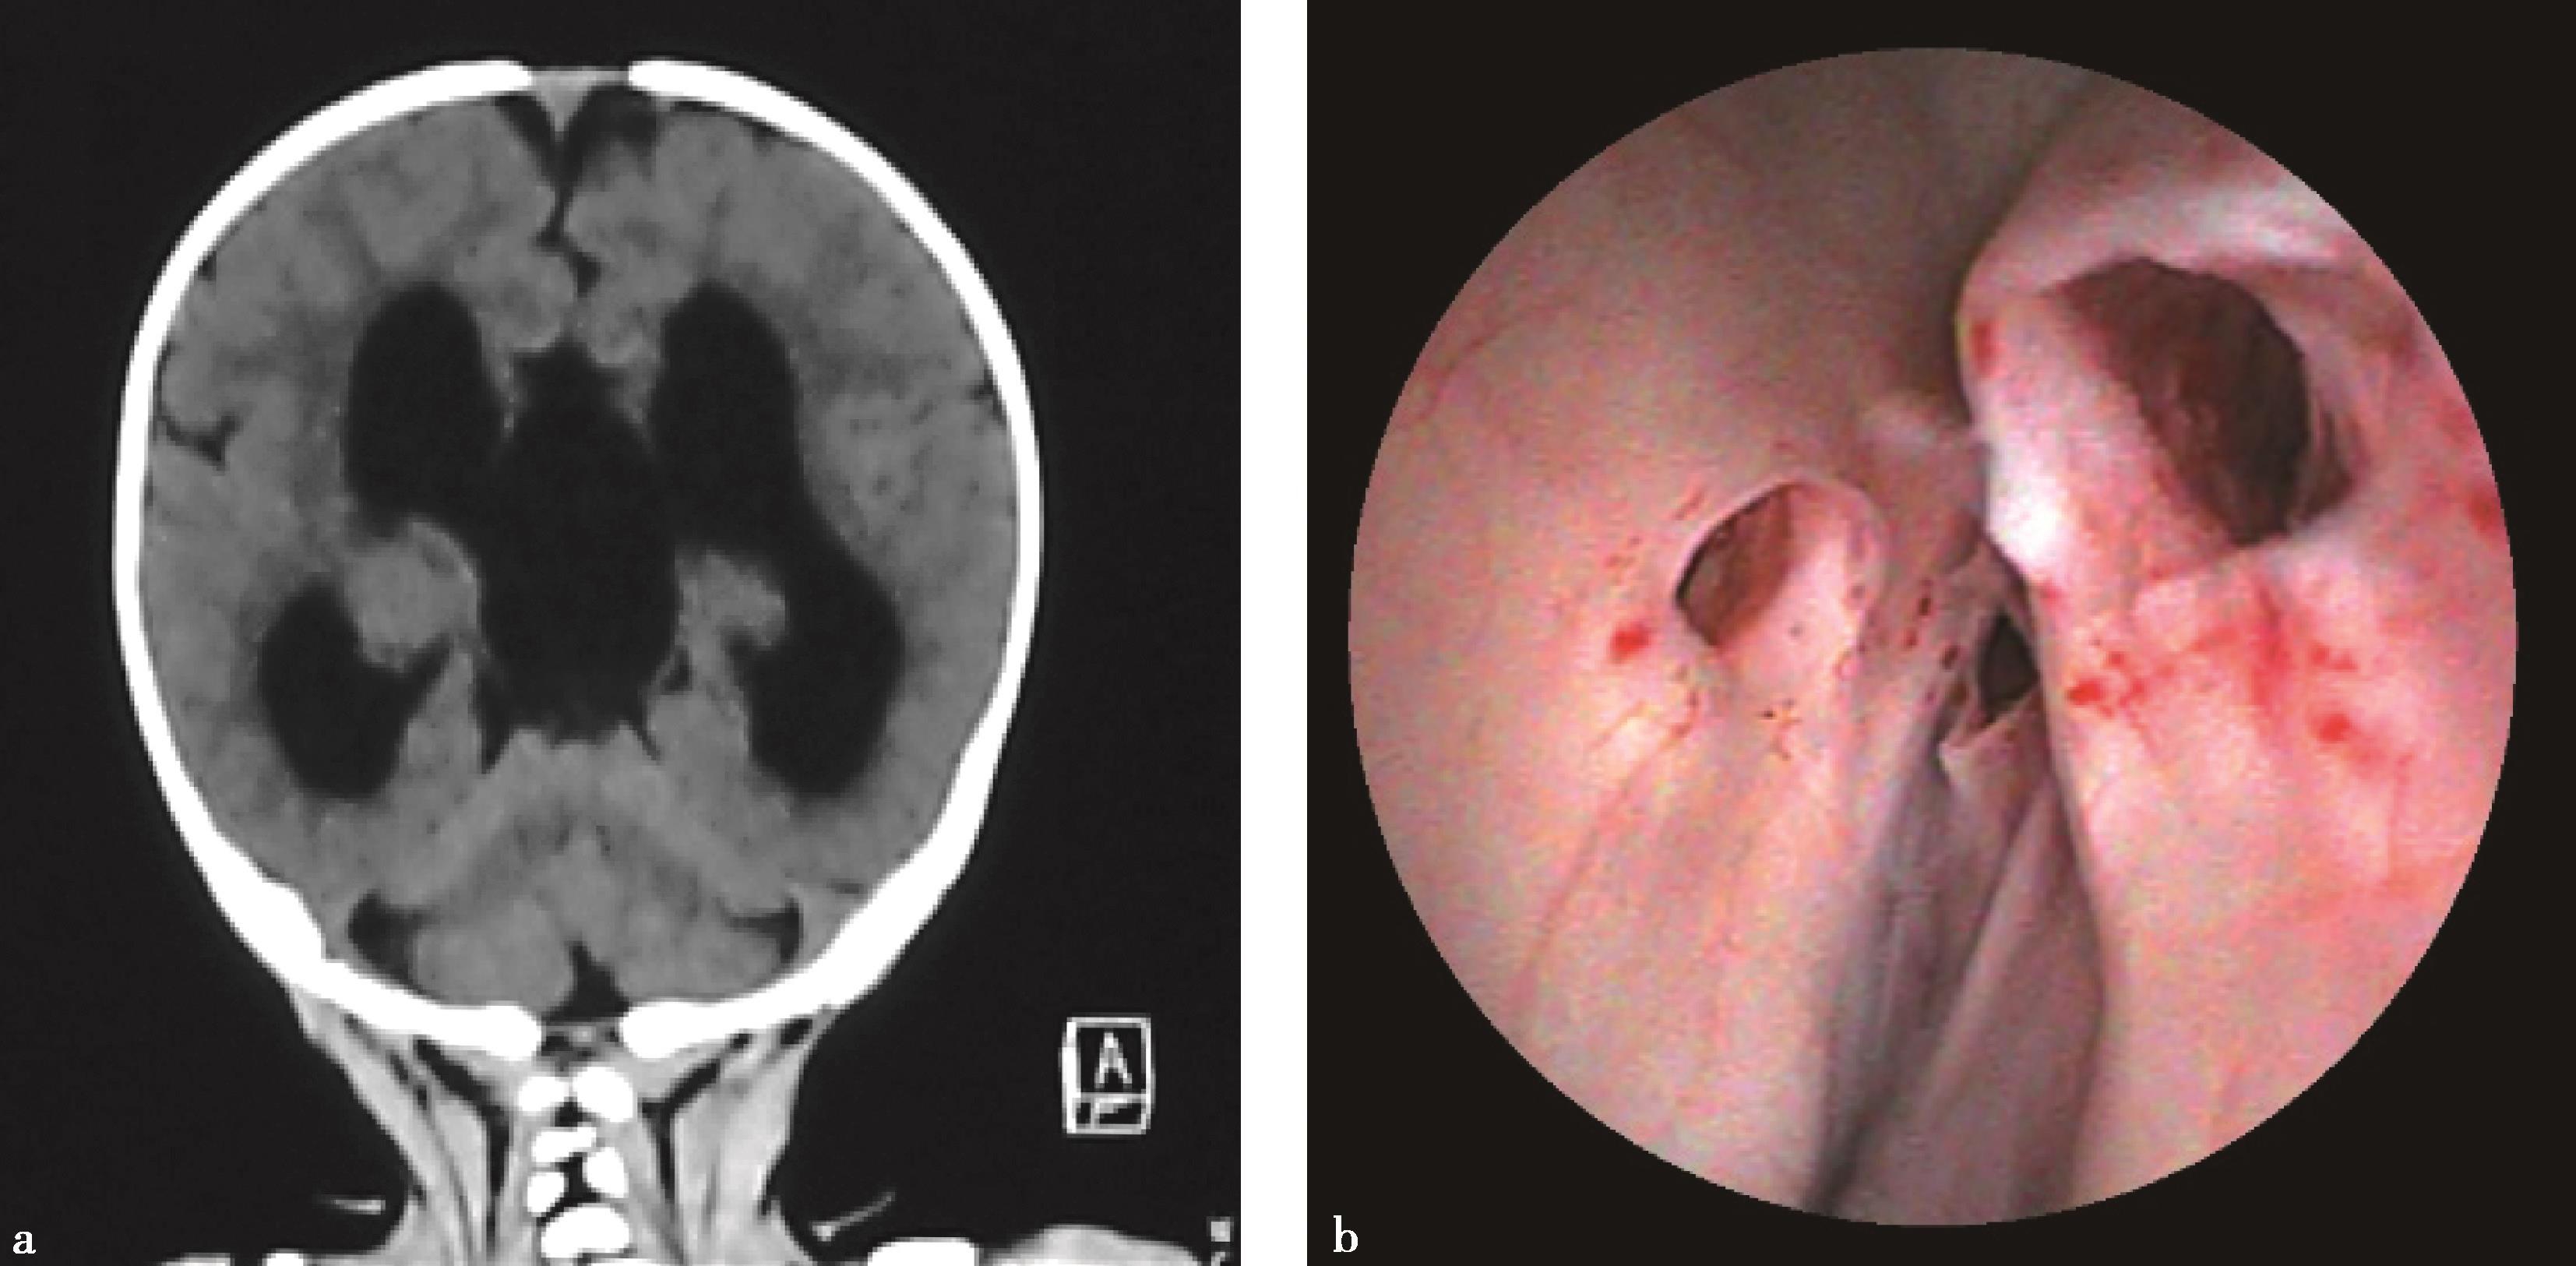

10.有些合并Chiari畸形的脑积水,单纯行内镜下第三脑室底造瘘术,改变颅腔和脊髓蛛网膜下腔之间的压力梯度后,下疝的小脑扁桃体可以还纳,临床症状缓解(图 3-1-2-11)。

图3-1-2-11 脑积水合并Chiari畸形

a.术前MRI矢状位片示脑积水,小脑扁桃体下疝;b.第三脑室底造瘘术后1周,MRI矢状位片示小脑扁桃体下疝减轻